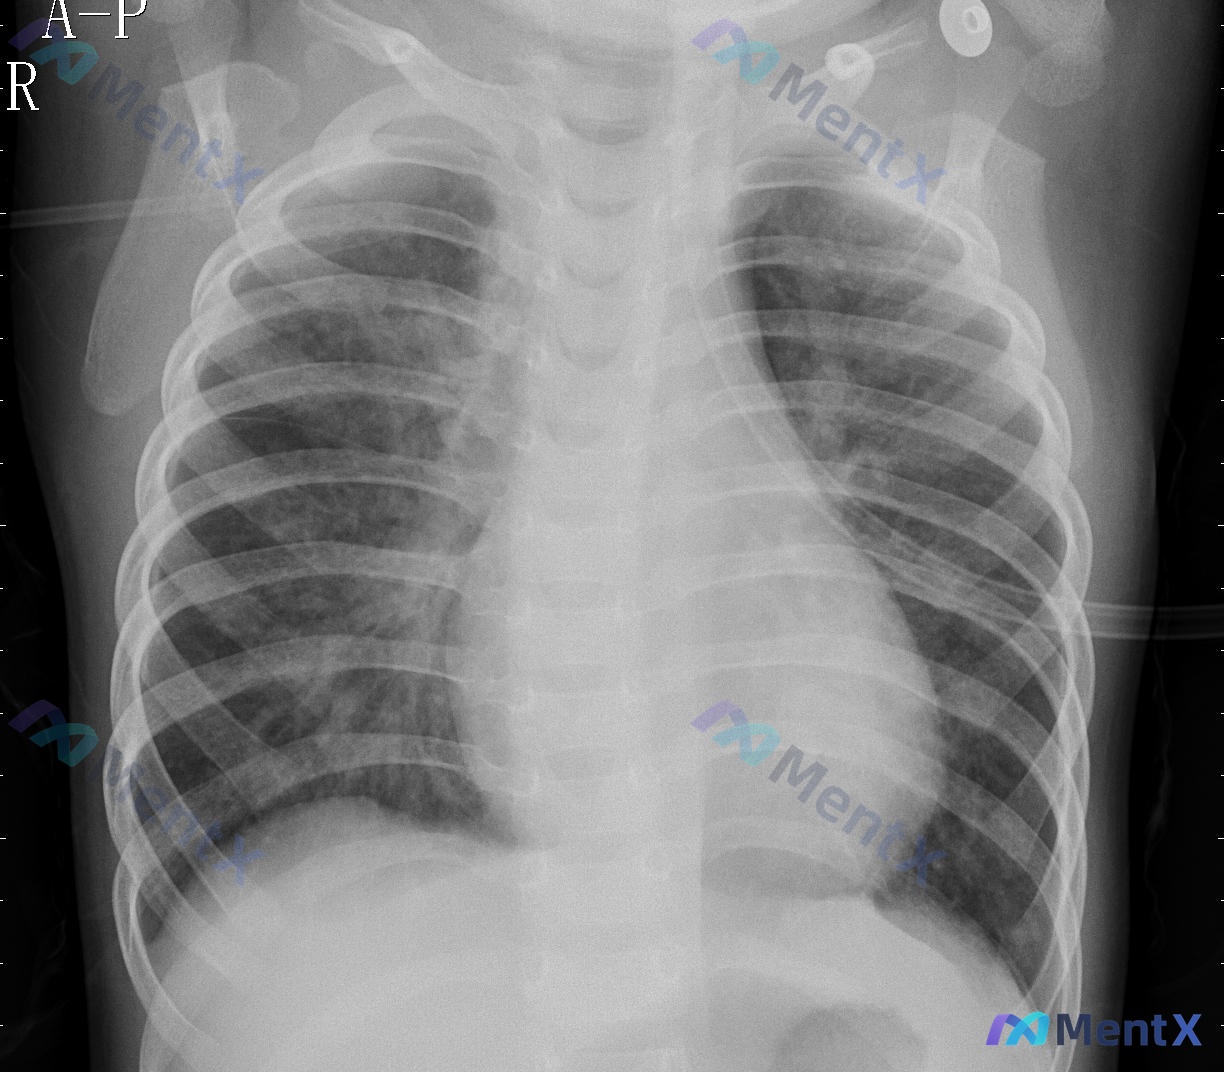

整理了一份儿童胸部X光片的分析资料,先不说结论,大家先看看前期表现的思路会不会分叉? 基础情况:儿童,胸部正位/前后位(A-P,床旁摄片常见)。 影像关键表现: - 气管纵隔居中,双侧肺野透亮度对称,无明显实变/空洞/肿块; - 双侧肺纹理较丰富,主要集中在肺门周围及内中带; - 心影比例看起来较大...